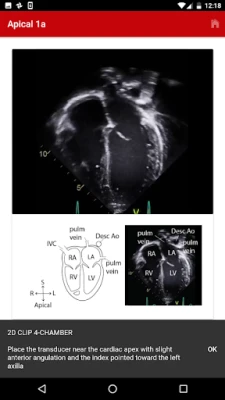

The Echo app provides step-by-step instructions for performing a normal pediatric echocardiogram and uses video clips, images and illustrations to aid in instruction. The app is intended to be used by sonographers at all levels of training, pediatric cardiology fellows, as a teaching aid for pediatric cardiologists and by anyone interested in learning how to perform the normal pediatric echo exam.

There are four standard views where images can be obtained:

1. Subcostal

2. Parasternal

3. Apical

4. Suprasternal

The exact images and the order in which the images and views are obtained varies by institution. Each protocol (subcostal, parasternal, apical or suprasternal) can be followed in order by clicking on the next tab at the bottom of the page or you can click on an individual numbered view within the protocol list to be taken directly to that view. The name of the view and instructions will pop-up automatically at the bottom of the page. The instructions and additional notes can also be found in the “NOTE” button at the bottom of the page.